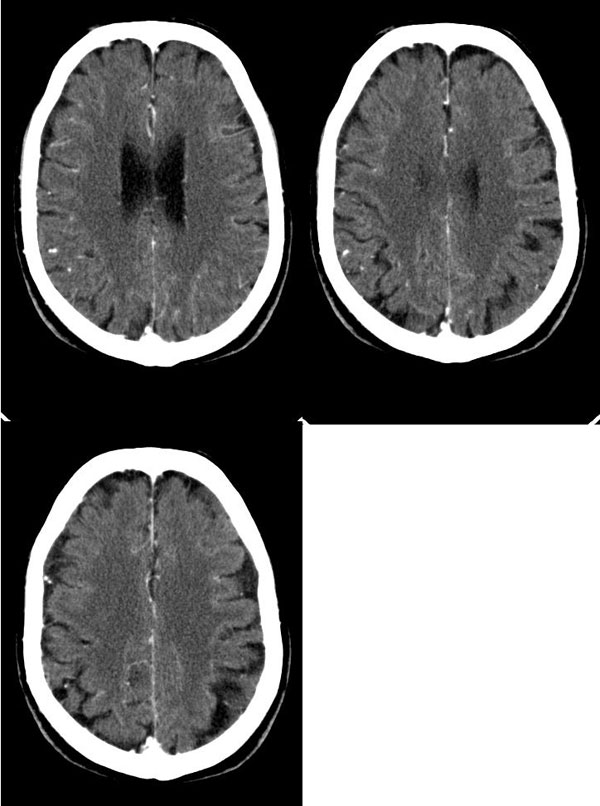

病人头晕12天,无视力障碍及肢体活动障碍

病灶平扫ct值约38hu,强化后明显强化,ct值约63hu,有一层ct值约72hu,病史:病人,男75,血压120/75,不高,头晕12天,平时体健,当时曾作胸x线片,正常。腹部ct,肝多发囊肿。经治疗(林格液+甘露醇)未用营养液及化疗药,当时诊断转移瘤。12天复查片如下

平扫:左侧颞枕叶内(左侧脑室后角旁)片状或楔形低密度影,内见条片状略高密度影,脑室无受压征象.

增强:条片状影均匀强化.

意见:考虑左侧颞枕叶梗塞.